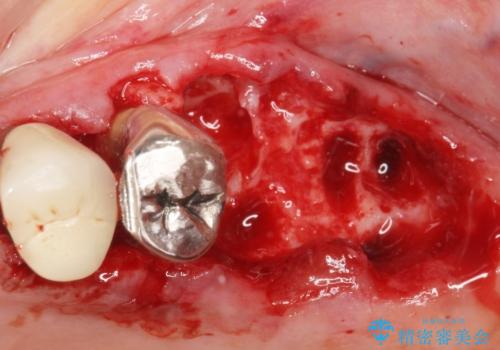

「抜歯したくない、インプラントは嫌」という患者様のご希望とご年齢を考慮し、可及的な骨外科処置や根分割術によりできるだけ今ある歯を残す治療方針をたてました。

保存不可能な左上の奥歯2本(左上67)は抜去し、ノンクラスプデンチャーをいれることにしました。

長期的な予後は保証できないことをご了承頂いた上で治療を行いました。